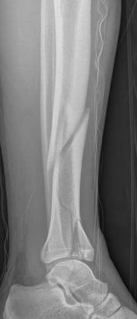

The management of complex tibial shaft fractures with extension into the distal articular surface (the tibial plafond or pilon) represents one of the most formidable challenges in orthopedic traumatology. These injuries typically result from high-energy mechanisms, such as a fall from a significant height or a motor vehicle collision, where axial loading forces are combined with severe rotational and shear vectors. The classic presentation, as highlighted in our index case of a 26-year-old male who fell 3 meters into a hole, involves not only catastrophic bony disruption but also devastating injury to the surrounding soft tissue envelope. The delicate nature of the soft tissues in the distal third of the leg, characterized by sparse muscular coverage and a precarious vascular supply, dictates the entire trajectory of clinical decision-making.

When a diaphyseal fracture propagates into the distal articular block, the injury transcends the typical treatment algorithms reserved for isolated tibial shaft fractures. Intramedullary nailing, the gold standard for diaphyseal fractures, becomes fraught with complications such as articular malreduction, propagation of intra-articular fracture lines, and inadequate distal fixation. Therefore, plate fixation—often utilizing minimally invasive percutaneous plate osteosynthesis (MIPPO) techniques—emerges as the primary definitive treatment modality. In the setting of an AO/OTA 43C3.3 fracture, where the articular surface is multifragmentary and completely dissociated from the diaphysis, the surgeon must meticulously reconstruct the joint surface before bridging the diaphyseal segment.

Pre-operative planning is the cornerstone of successful execution in complex pilon-variant tibial shaft fractures. The surgeon must transition from a conceptual understanding of the injury to a concrete, step-by-step surgical blueprint. This begins with high-quality orthogonal radiographs of the entire tibia, ankle, and knee. However, plain films drastically underestimate the degree of articular comminution and central impaction. A fine-cut computed tomography (CT) scan with 2D multiplanar reformats (coronal and sagittal) and 3D surface rendering is absolutely mandatory.